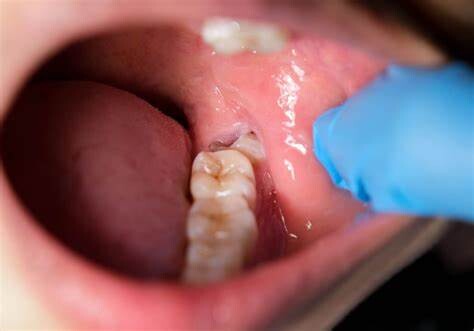

Any type of surgery is scary, and it is natural for people wanting to postpone the surgery as long as possible. Similar is the case with a dental procedure, it can be daunting too. You might be postponing due to various reasons – as you will have to encounter wisdom teeth removal cost, you might have to avail a day’s leave for the procedure, and above all you are frightened!

But, this delay can be really dangerous and can have serious consequences on your health. Here are a few reasons as to why delaying the wisdom teeth removal can be a bad idea:

Wisdom teeth promotes Gum Disease

It is a challenging task to clean the area in which the third molars have erupted. Therefore they are at a greater risk of acquiring the periodontal problems. The gum diseases are usually caused by bacteria, and when a tooth can’t be precisely cleaned on a regular basis, the dental plaque gets accumulated around the tooth, which may lead to further complications.

Tooth Decay

The fully impacted or the partially impacted wisdom teeth are at greater risk of tooth decay, than other teeth. This usually happens, because of the location of the wisdom tooth, especially towards the back of the mouth, which is hard to clean. Moreover, since it lies at the back of the mouth, there are chances of food getting easily trapped between the gums and the tooth, promoting the growth of bacteria.

You can’t prevent the occurrence of an impacted wisdom tooth, but with a regular dental check-up, your dentist will help you monitor the emergence of the wisdom tooth, with the help of dental X-rays and advanced methodologies, which might indicate the need of wisdom teeth removal.